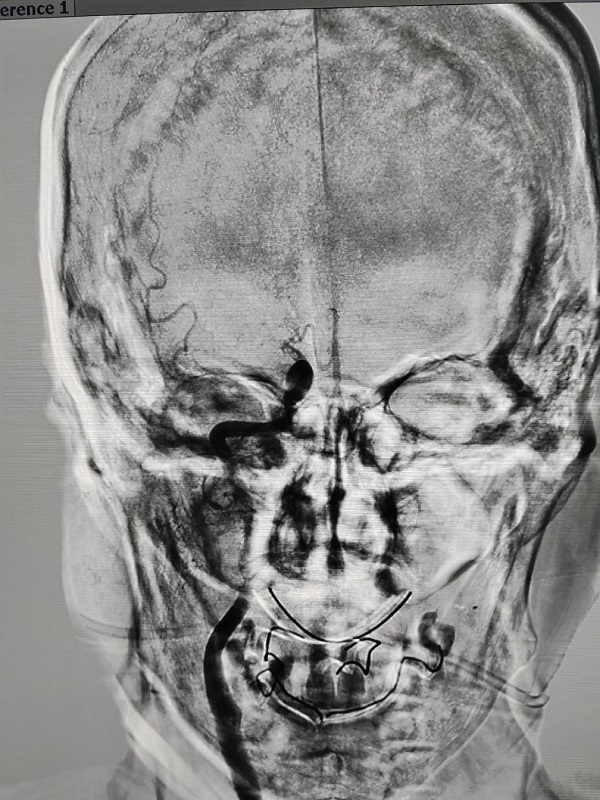

入院时,姬阿姨意识不清,言语混乱,呈昏睡状,左侧上、下肢肌力0级,NIHSS(一种卒中量表)评分高达12分。王建峰主任团队立即开启脑卒中绿色通道,在对姬阿姨病情完整评估后,迅速进行全面的头颅CT检查,CT提示姬阿姨颅内双侧基底节区腔梗(脑梗塞的一种-图1)。经仔细评估,结合既往病史、发病特点及头颅CT所示,王建峰主任团队推断姬阿姨应是心源性脑栓塞,可能需要进一步手术治疗。但颅内动脉取栓最佳时间是发病后6小时内,而姬阿姨是睡醒后卒中,无法明确具体发病时间,此时若盲目进行手术可能造成颅内过度灌注(脑血流明显增加、超过正常水平)引起脑出血,反而加重病情。但若不行手术治疗,随着时间延长,病情会越发严重,甚至脑疝形成危及生命。

图1